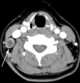

Necrotic lymph node metastasis

Lymphadenopathy or adenopathy is a disease of the lymph nodes, in which they are abnormal in size or consistency. Lymphadenopathy of an inflammatory type (the most common type) is lymphadenitis, producing swollen or enlarged lymph nodes. [Source: Wikipedia ]